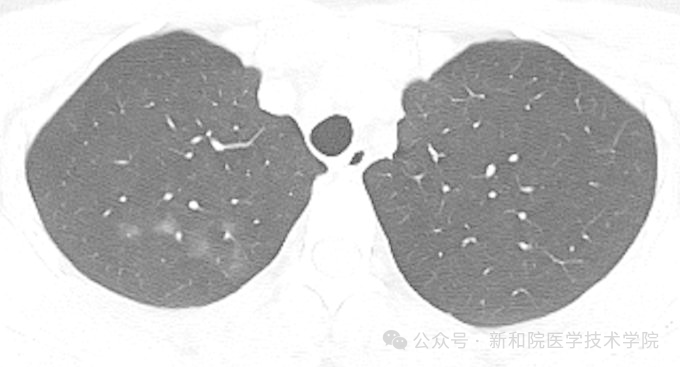

1号嫌疑人:【磨玻璃结节 (GGN)】—— 窗户上的薄雾

【侦探描述】 它在CT上看起来像块云雾状的淡薄影,就像窗户玻璃蒙了一层水雾,还能模模糊糊看到下方的血管轮廓。

【身份揭秘】 它是最让人纠结的“双面镜”。

良性可能: 可能是病毒性肺炎、肺水肿这类良性炎症留下的痕迹。

恶性可能: 也可能是原位腺癌等早期肿瘤的信号。

【关键对策】 别自己吓自己,关键是遵循医嘱,定期复查看变化。